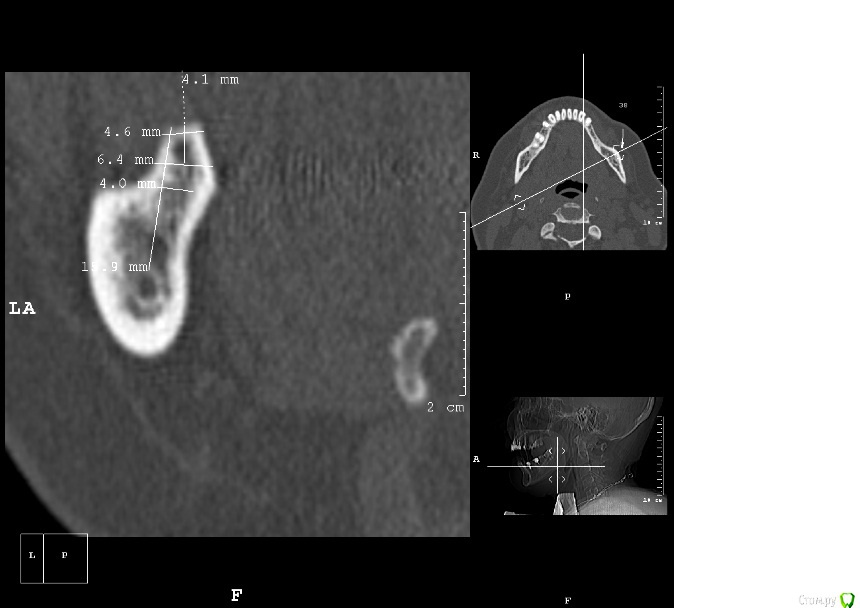

kamranchick Опубликовано 25 апреля, 2016 Поделиться Опубликовано 25 апреля, 2016 Пациентка обратилась с целью восстановления жевательного отдела.финансовый вопрос не интересует, хотелось бы чтобы с минимальными рисками.1.я думаю - удаление, 3 винта, сосидж, 5 пинов.чтобы вы предложили? Ссылка на комментарий

kamranchick Опубликовано 2 мая, 2016 Автор Поделиться Опубликовано 2 мая, 2016 ну я указал 3 сегмент, 3 винта, следовательно удаление 5 го зуба, установка имплантатов в область 35 36 и 37 Ссылка на комментарий

kamranchick Опубликовано 1 февраля, 2017 Автор Поделиться Опубликовано 1 февраля, 2017 Аугментата пожалели мне кажется, объёма не особо добавится. Почему винты сразу не захотели? Вроде кости много.Побоялся что если что то пойдет не так то придется все выгребать))Кости если честно не пожалел, не знаю куда он ушел, была ауто кость 2 грамма gen os и 0 5 альфа био графта Ссылка на комментарий